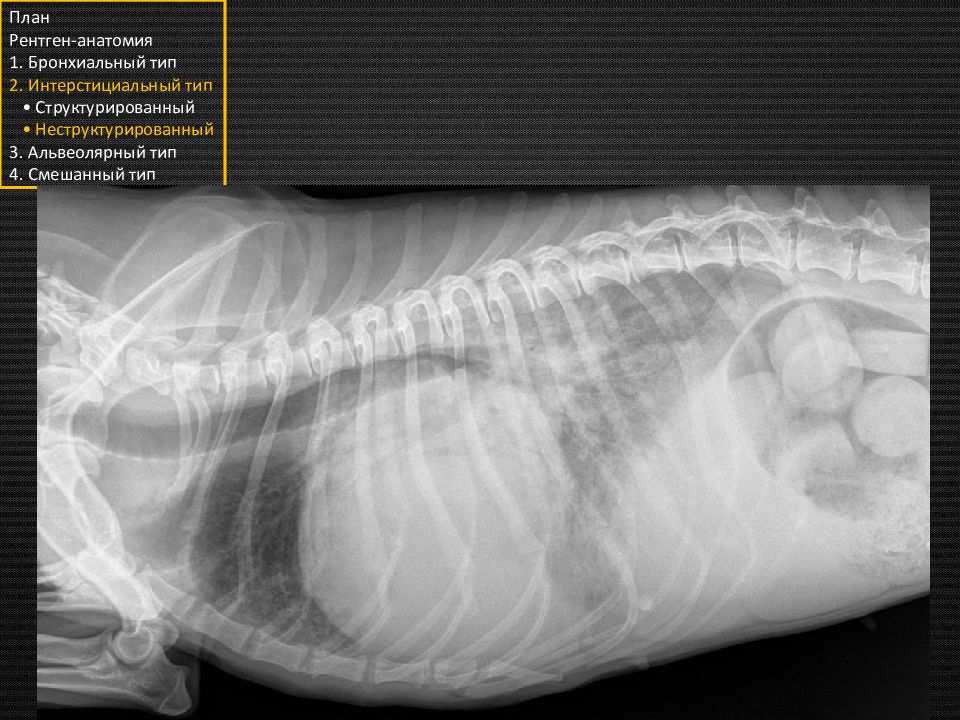

Собака. Грудная клетка нормальной формы План Рентген-анатомия 1. Бронхиальный тип 2. Интерстициальный тип • Структурированный • Неструктурированный 3. Альвеолярный тип 4. Смешанный тип